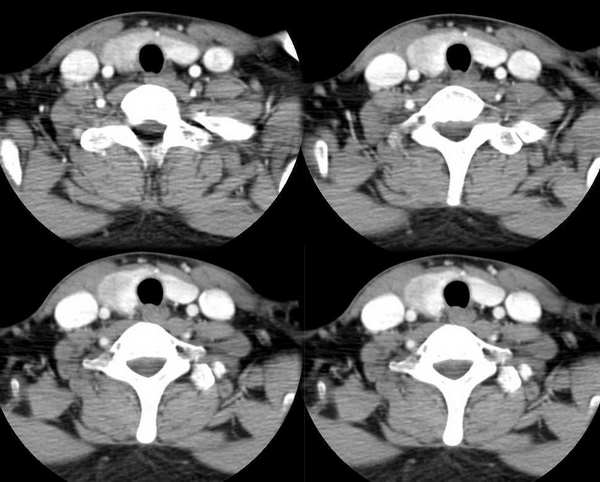

男,25岁,体温39.3度,发现右侧颈部包块.

右侧甲状腺内边界不甚清楚之占位,增强强化不很明显,无钙化。考虑腺瘤,建议活检,除外ca。

肿块还是有强化的,会不会是甲状腺癌呢?但是体温39.3度不好解释,等待高手发言

左侧甲状腺肿大,增强时较对侧密度低。考滤炎症可能性为大。这种病灶要用影象检查时还算彩超较ct为好

右侧甲状腺内边界不甚清楚之占位,增强后呈轻度强化。

1.考滤炎性病变可能性大;2.不除外ca。

此病例特点:1、年轻男性,基本上是高热;2、右侧甲状腺肿大呈边界不清之低密度,但甲状腺境界清晰;3、基本没有增强但低密度的周边略呈边缘增强反应;4、最好补充病史:痛否?时间?(如痛、急性起病。)

据此,以甲状腺急性炎症可能性大。